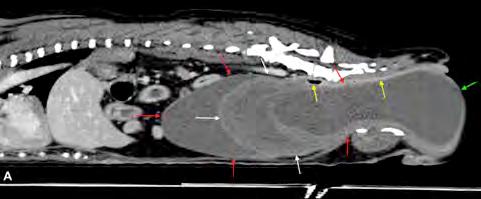

Figura 1. ECDM. (A) Medida mediante MOD del volumen del AI. (B) Corte paraesternal derecho 4 cámaras, zoom AI. Ratio LA/BW = 3, 8 ml/kg.

Se excluyeron del estudio los pacientes con patologías concomitantes a la ECDM, tanto cardíacas como de otros sistemas orgánicos, excepto la presencia de hipertensión pulmonar estimada mediante ecocardiografía. Se realizó la medición del volumen del atrio izquierdo con el método monoplano sumatorio de discos (MOD)9 a partir de la técnica de Simpson, que consiste en la medición del volumen del AI mediante la suma de los volúmenes de diferentes discos contiguos perpendiculares al eje mayor del AI generados por el software del ecógrafo, tras trazar el área del AI y su eje mayor de forma manual. Esta medición se realizó desde el corte paraesternal derecho longitudinal de 4 cámaras en telesístole, previo a la apertura de la válvula mitral (Fig. 1). Se siguió el borde endocárdico del atrio izquierdo, previo a la apertura de la válvula mitral en la telesístole cardíaca, sin incluir las venas pulmonares. Posteriormente, lo correlacionamos con el peso del paciente realizando la ratio: LAv/BW = volumen del atrio izquierdo (ml) / peso del paciente (kg).1,2,6